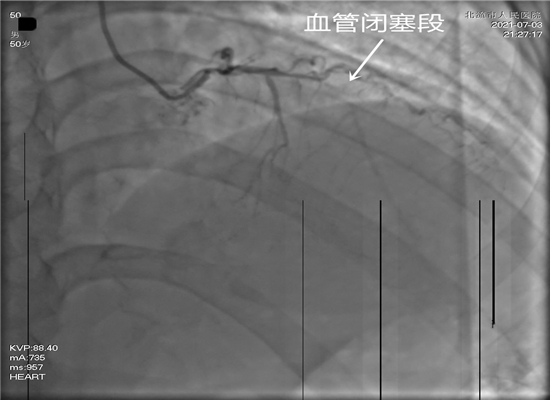

病人转送至导管室,准备手术

时间就是生命,这是一场与死神生死竞速的硬仗。21时15分,病人进入导管室,在赵子粼博士的主持下,张轩副主任亲自操刀,介入团队密切配合,快速穿刺桡动脉、置管、造影,升压,开通闭塞血管,植入支架。经过约50分钟的全力救治,成功挽救了患者的生命。目前,术后患者症状明显改善,恢复较好。

放支架前,显示血管闭塞